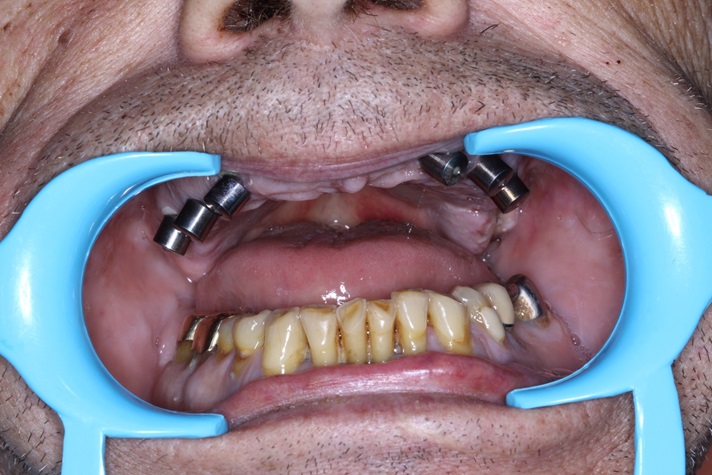

Tall and Tilted Pin Hole Immediate Loading ( TTPHIL) is a modern and most reliable technique for dental implantation. The special feature of such method is that dentist combine long and wide implants with bi-cortical support bone.

This technique also use immediate loading so the implants are placed right after teeth extraction.

First and foremost is that there is no stitches and no flap raising. In addition, after dental implantation with TTPHIL method, no antibioticsare  required. It is a great mild painkiller with no blood loss. Many dentists use immediate loading because the whole surgery takes about 30 minutes. This technique is highly applicable for heart and diabetic patients.  TTPHIL is very popular because it has 99% success rate.  Lifetime warranty* is one of the most important advantage both for dentists and patients.

This case report show the successful All on 6 dental implantation using Alpha Dent implants.